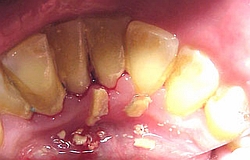

Parodontitis = akute Zahnfleischentzündung kann auch bei guter Pflege entstehen, sehr schmerzhaft und beeindruckend aber schnell heilbar ohne Verlust

Parodontose = chronische Zahnfleischentzündung mit Knochenverlust und Verlust des Zahnhaltes bei fortgeschrittenem Zustand. Muss über einen längeren Zeitraum immer wieder kontrolliert werden.

Zu spät bei Parodontose ?

Kommen Sie zum Zahnarzt auch im schlimmen Zustand, zusammen mit dem Behandler kann oft auch noch in weit fortgeschrittenen Fällen geholfen werden und die Zähne noch lange schmerzfrei erhalten bleiben. Es ist nie zu spät- schlimmstenfalls kann mit Zahnersatz und oder Zahnimplantaten geholfen werden.